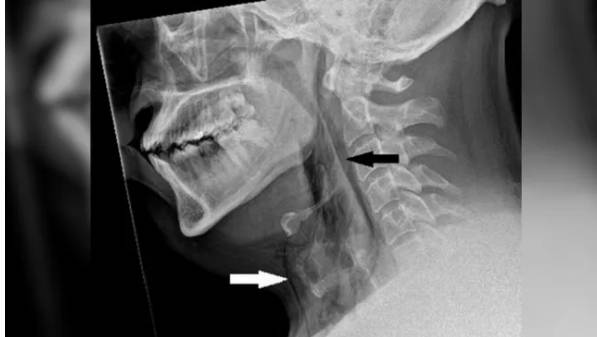

![기관지가 찢어진 남자의 X-선 이미지로 흰색과 검은색 화살표 부위가 피부 아래에 갇힌 공기 영역이다. 재채기를 참다 기관지가 찢어진 첫 사례다. [BMJ Case Reports 캡쳐]](https://img2.daumcdn.net/thumb/R658x0.q70/?fname=https://t1.daumcdn.net/news/202505/24/KorMedi/20250524085218557xowh.jpg)

이 남성은 숨을 쉬거나 음식을 삼키거나 말하는 데 아무런 문제가 없었다. 의료진은 그의 목을 검사하면서 희미하게 딱딱거리는 소리를 들었다. 엑스레이를 찍어보니 공기가 피부 아래 조직에 갇힌 상태인 외과적 폐기종의 징후가 있었다.

CT 스캔 결과 이 환자는 목의 세 번째와 네 번째 뼈 사이가 찢어져 있었다. 공기가 목의 조직과 폐 사이 공간으로 빠져나갈 수 있었다. 구멍 크기는 가로 세로 약 2mm 정도였다.